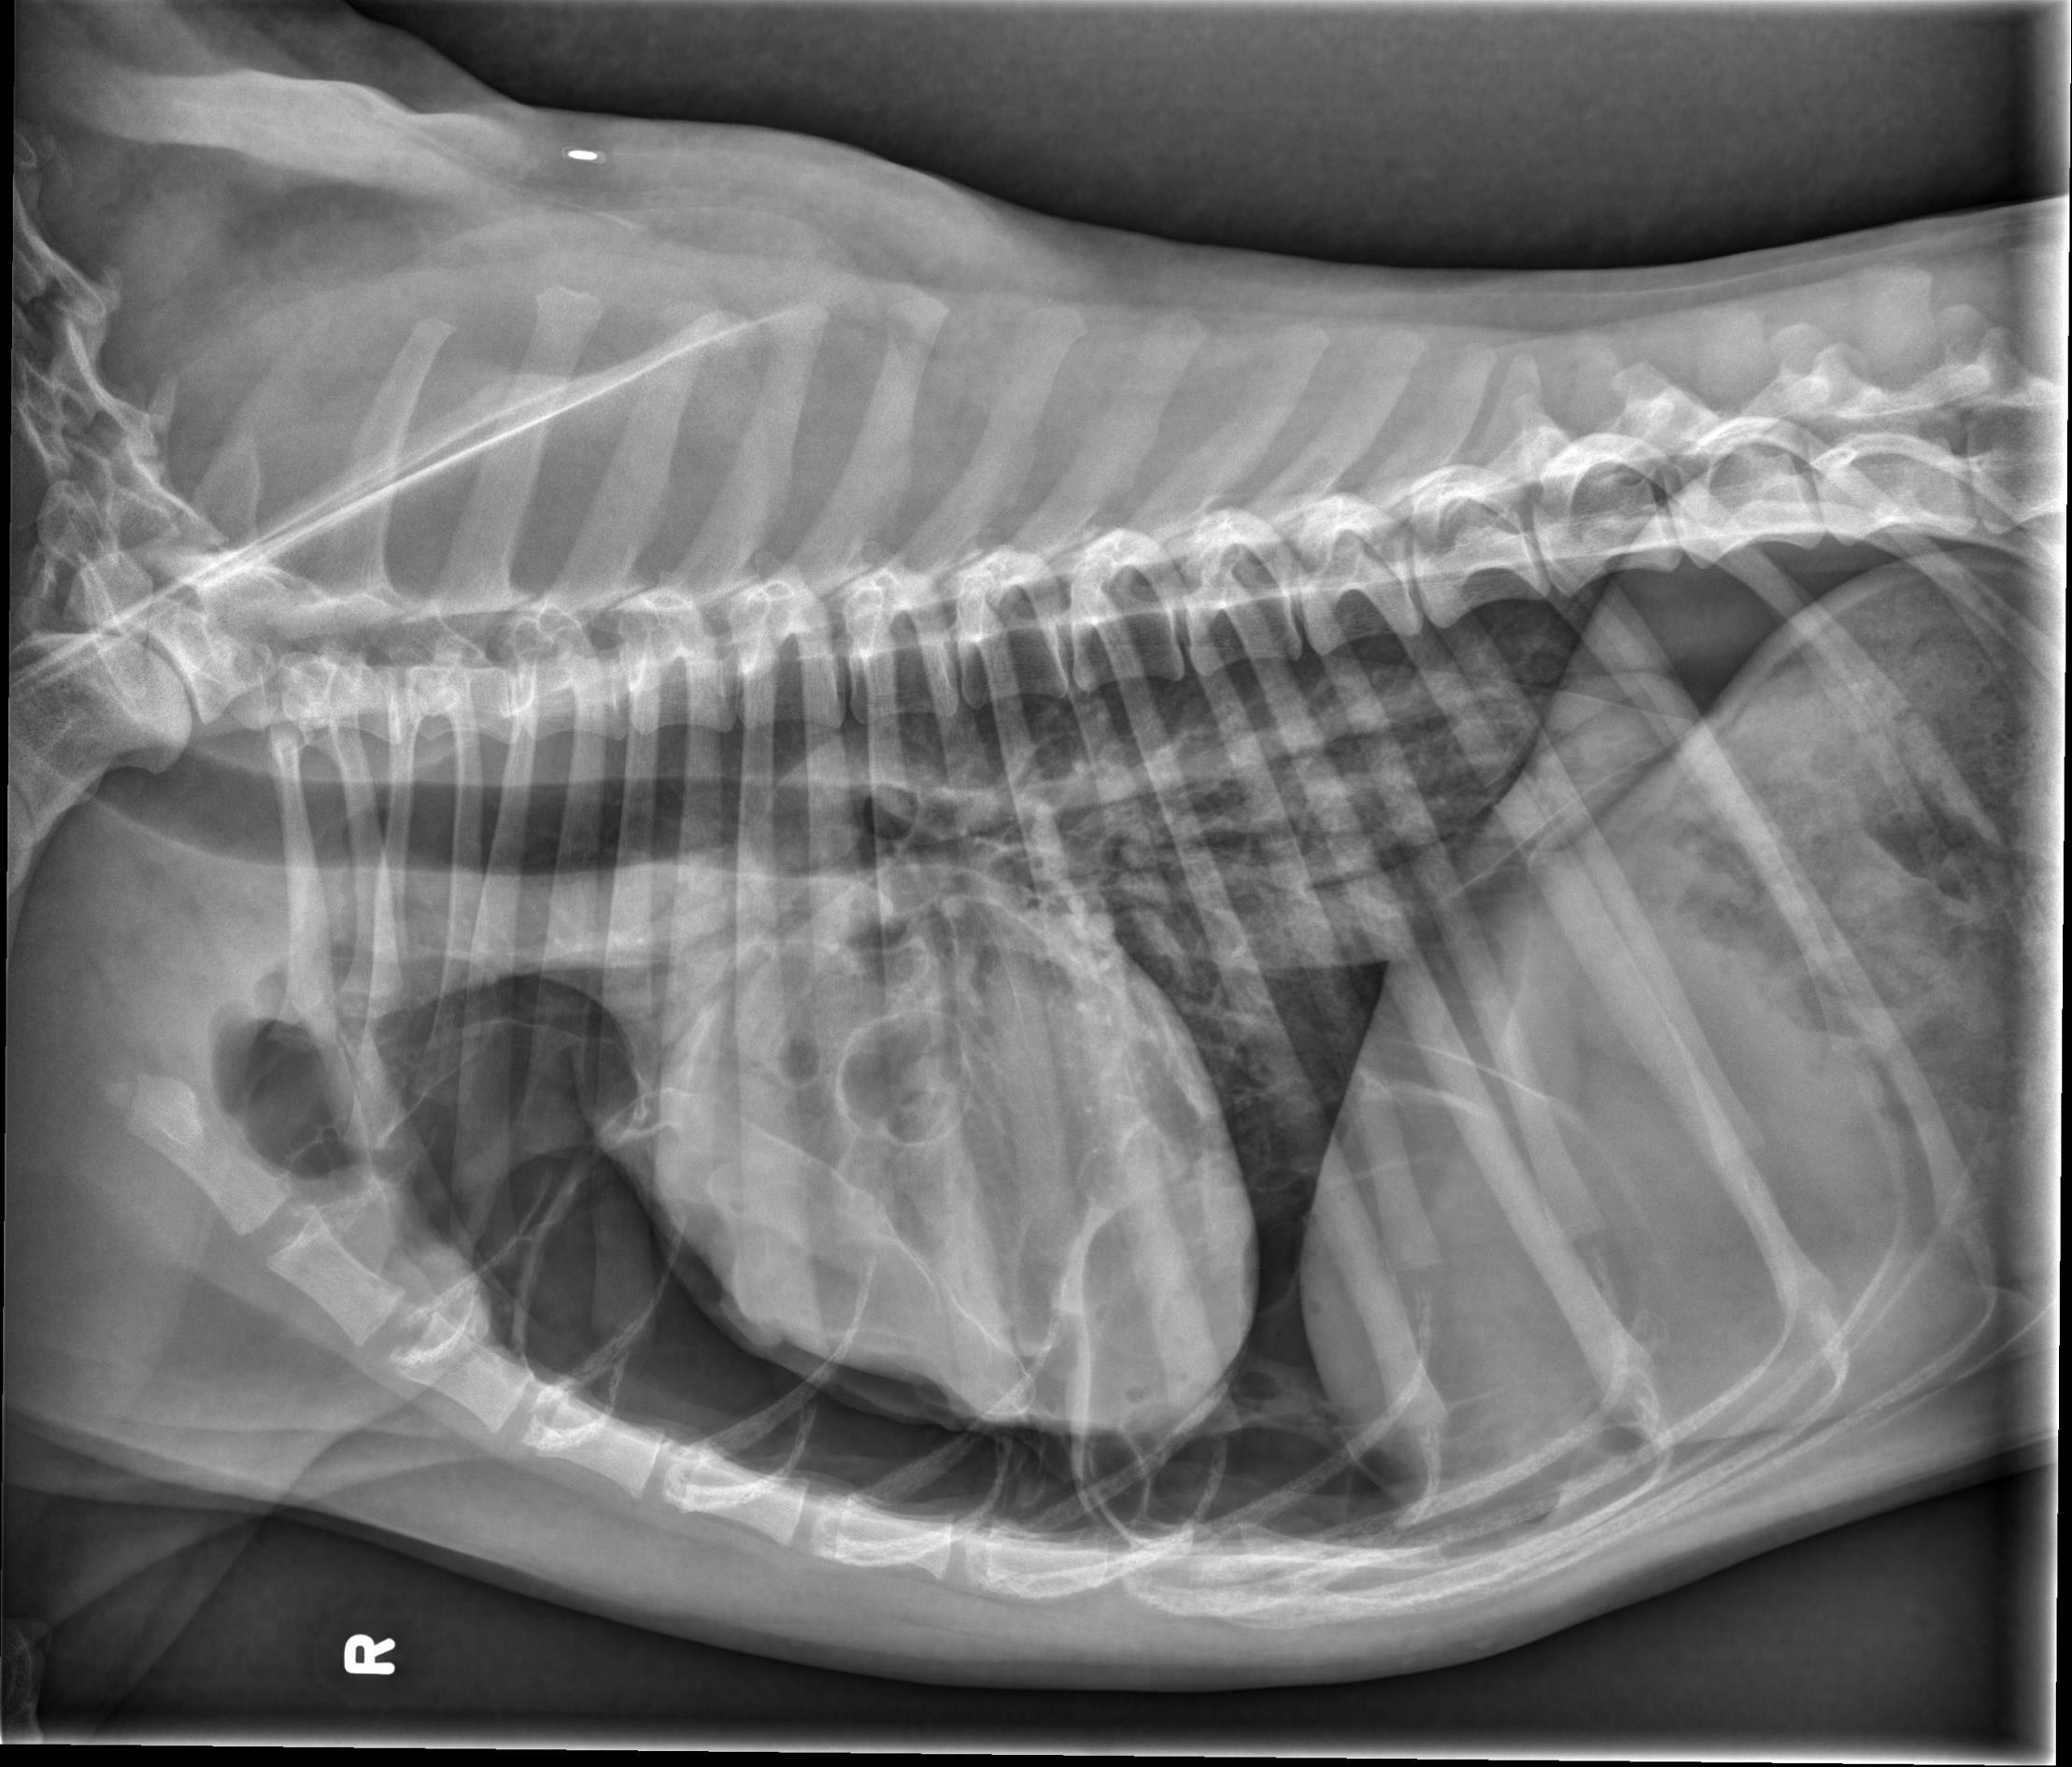

Thorax- ventrodorsal and opposite lateral radiographs are available for review.

There is a large volume of gas in the pleural space, bilaterally, with retraction of the pulmonary margins from the body wall. A smaller volume of fluid is also present. In the caudal subsegment of the left cranial lung lobe, there are two well-defined, gas filled structures with a thin, soft tissue opaque rim. The largest measures 2.7cm in diameter, and the smaller, located just cranial to the first measures 0.9cm in diameter. There is an alveolar pulmonary pattern in the ventral aspect of the right cranial lung lobe with an air bronchogram, most prominent on the left lateral projection. Throughout the remainder of the pulmonary parenchyma, there is a mild to moderate, diffuse, unstructured interstitial pulmonary pattern. Dorsal to the second and third sternebrae, there is an ovoid soft tissue structure consistent with an enlarged sternal lymph node (up to 1.6cm in thickness). The stomach contains a moderate volume of heterogenous soft tissue opaque material and gas. The musculoskeletal structures included in collimation are normal.

At least two pulmonary bullae. There is no reported history of trauma, and with the presence of at least two other pulmonary bullae, spontaneous pneumothorax secondary to ruptured bulla is possible.

Alveolar pulmonary pattern in the right cranial lung lobe may represent a focal region of more severe atelectasis (secondary to pneumothorax), however, given the history, underlying pulmonary pathology such as resolving pneumonia is also considered. The pulmonary pattern in the remainder of the lung lobes is consistent with atelectasis.

Mild to moderate sternal lymphadenopathy, likely reactive.

Gastric ingesta may be digestible or indigestible. Evidence of obstruction is not currently identified.